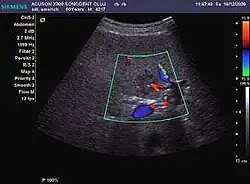

The ultrasound appearance is a well defined lesion, with very thin, almost unapparent walls, without circulatory signal at Doppler or CEUS investigation. The content is transonic suggesting fluid composition. The presence of membranes, abundant sediment or cysts inside is suggestive for parasitic, hydatid nature. Posterior from the lesion the acoustic enhancement phenomenon is seen, which strengthens the suspicion of fluid mass. They typically displace normal liver vessels but no vascular or biliary invasion occurs.